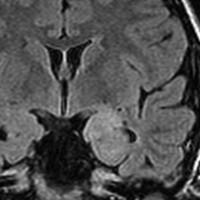

成人の頭頂葉の例

無症状で偶然発見されたものです。CTで石灰化があり,部分的にガドリニウム増強されます。乏突起膠腫グレード2との鑑別が難しい例です。乏突起膠腫より放射線化学療法に治療抵抗性ですから,もちろん治療選択は全摘出です。